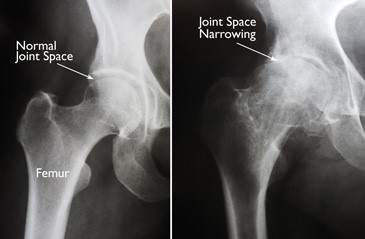

(Left) In this x-ray of a normal hip, the space between the ball and socket indicates healthy cartilage.

(Right) This x-ray of an arthritic hip shows severe loss of joint space.